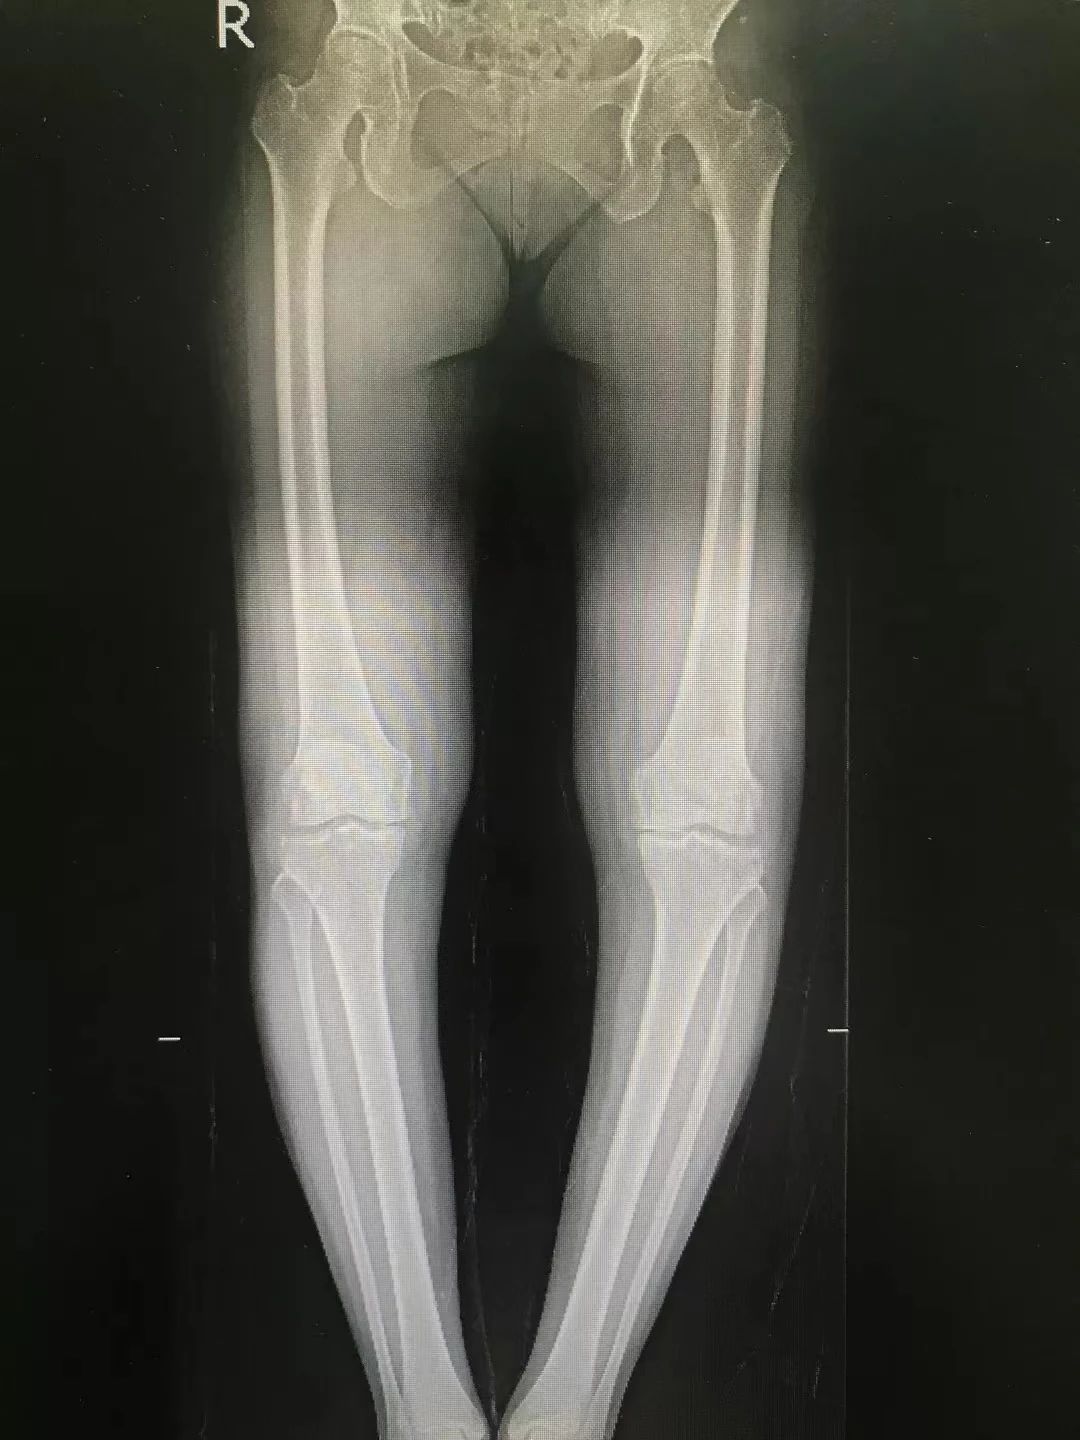

来自上海的李女士双膝疼痛10余年,左侧疼痛感更强烈,长期经口服消炎止痛药、理疗和关节腔注射玻璃酸钠等非手术治疗均收效甚微。在多处求医无门之后,李女士来到海南省人民医院运动医学科。经过王广积对其病情的仔细分析,诊断患者为双侧膝关节骨性关节炎,以内侧间室为重,左侧膝关节明显内翻畸形。

若按传统人工膝关节置换手术,可能会导致患者创伤大,且手术费用较高。考虑到患者较为年轻,后期或许还将面临二次或多次翻修手术。为了减少手术创伤及经济负担,王广积主任团队为患者开展了一期左侧胫骨高位截骨矫形术(HTO)和右侧单髁置换术(UKA)。“这是目前治疗膝关节骨性关节炎的有效的微创手术,在延缓膝关节炎的进展、改善关节功能的同时,还能最大程度减少手术创伤及费用。”王广积表示。